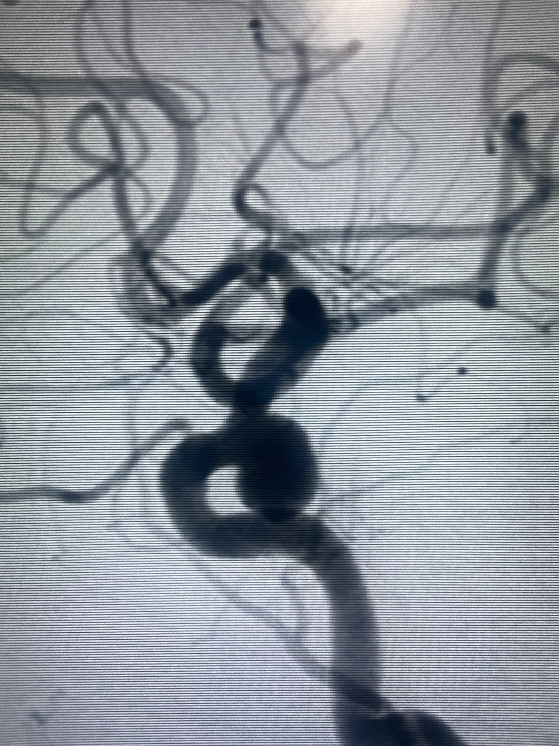

| Túi phình mạch máu não ở bệnh nhân qua kết quả chẩn đoán hình ảnh |

Tại bệnh viện, kết quả kiểm tra hình ảnh các bác sĩ phát hiện bệnh nhân có túi phình mạch não lớn (kích thước 7.7x5.3mm), cổ túi phình 5 mm, vị trí tại động mạch cảnh trong trái. Nếu không được can thiệp kịp thời túi phình sẽ vỡ khiến bệnh nhân tử vong.